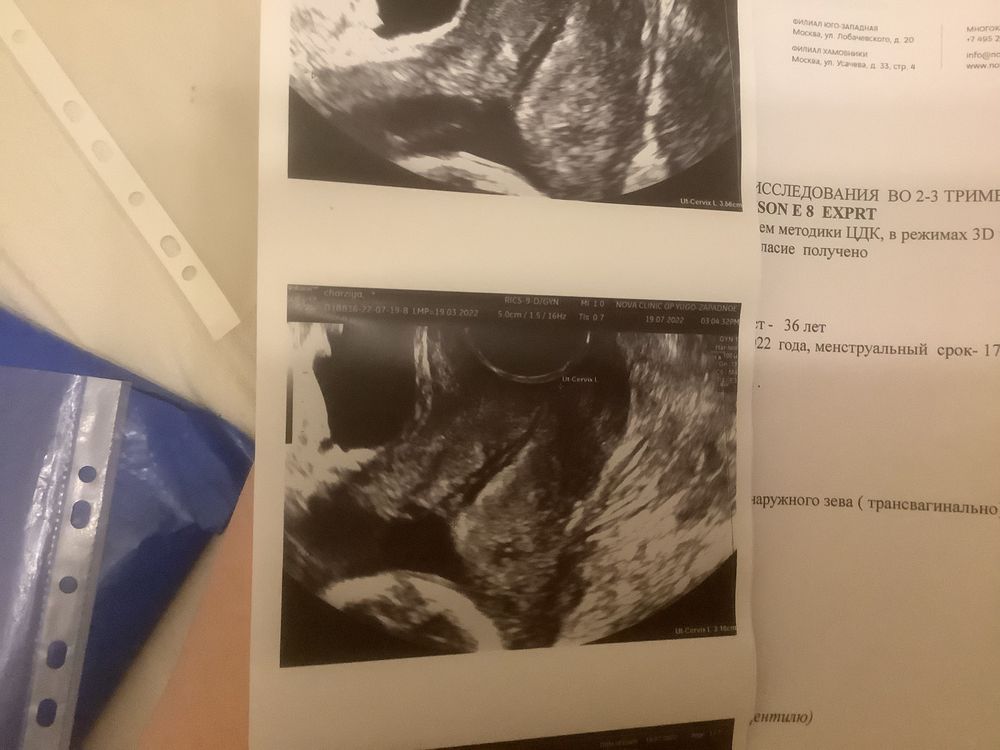

Девочки подскажите, беременность 17 недель,вчера сходил на платное узи смотрели шейку и кровотоки , шейка 32-35 мл , зев закрыт но визуально кажется что открыт так как там слизь. Вообщем все нор.м, как сказала узистка. Но я вчера начиталась как девочки теряют беременность за 10 дней так как шейку не мониторят, и у меня паника началась, теперь я не верю что у мен все нормально. Доктор в жк в отпуске она вообще назначала мне узи шейки 29 июня и теперь только скрининг 1 августа, и сказала что шейка должна быть минимум 35 мм. Кстате я на утрожестане 2 свечи 2 раза в день. Кто разбирается, мне паниковать или нет. ?!подскажите плиз

Я вижу на снимках, что цервикальный канал немного раскрыт, он должен быть сомкнут. Насколько это критично только с врачом